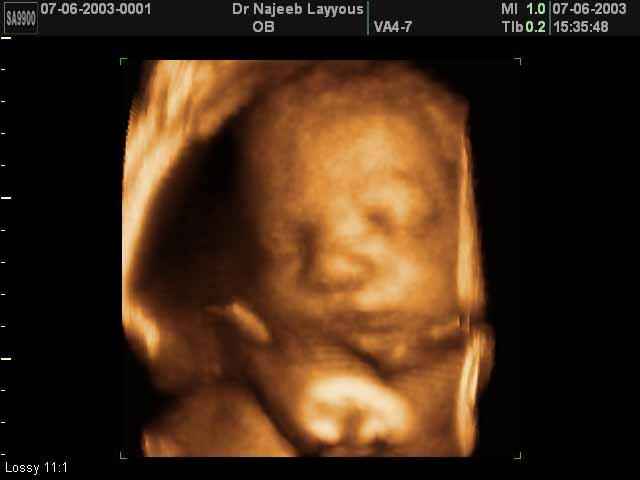

3D Fetal Face Ultrasound Scan Photos | Dr N Layyous

3D Fetal Face Ultrasound Scan Photos